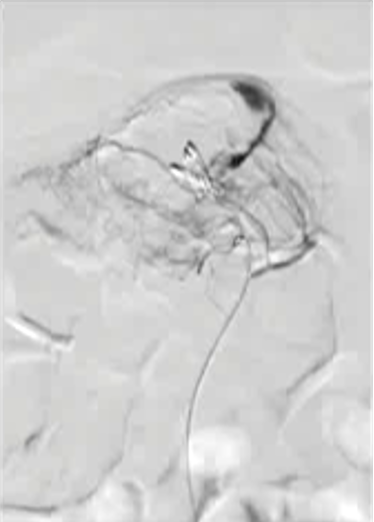

病例三 77岁女性复发性胃肠道出血,需要多次输血并入住ICU。(d)栓塞后无外渗。箭头指向栓塞部位。